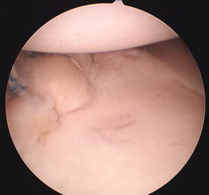

관절순 파열 수술 후